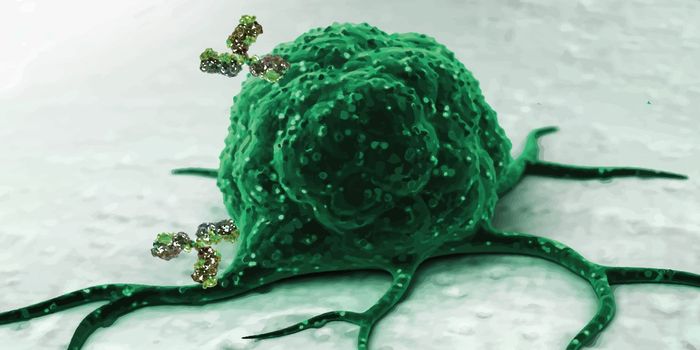

MAY 06, 2024ImmunologyPublished by Bindi M. Doshi, PhD In the realm of immunodiagnostics, antibodies have long been invaluable tools, e ...

FEB 22, 2024ImmunologyThe US Food and Drug Administration (FDA) recently approved a tumor-infiltrating lymphocyte (TIL) therapy referred to as ...

NOV 29, 2023CancerThe CAR-T Revolution: Developing T Cells into Cancer Assassins Cancer has long been a formidable foe, but recent ...

OCT 17, 2023CancerIntroduction CAR-T therapies represent a new successful strategy for the treatment of hematological malignancies; howeve ...

MAY 16, 2023CancerIntroduction Chimeric antigen receptor (CAR) therapies involve the use of engineered receptors capable of redirecting im ...